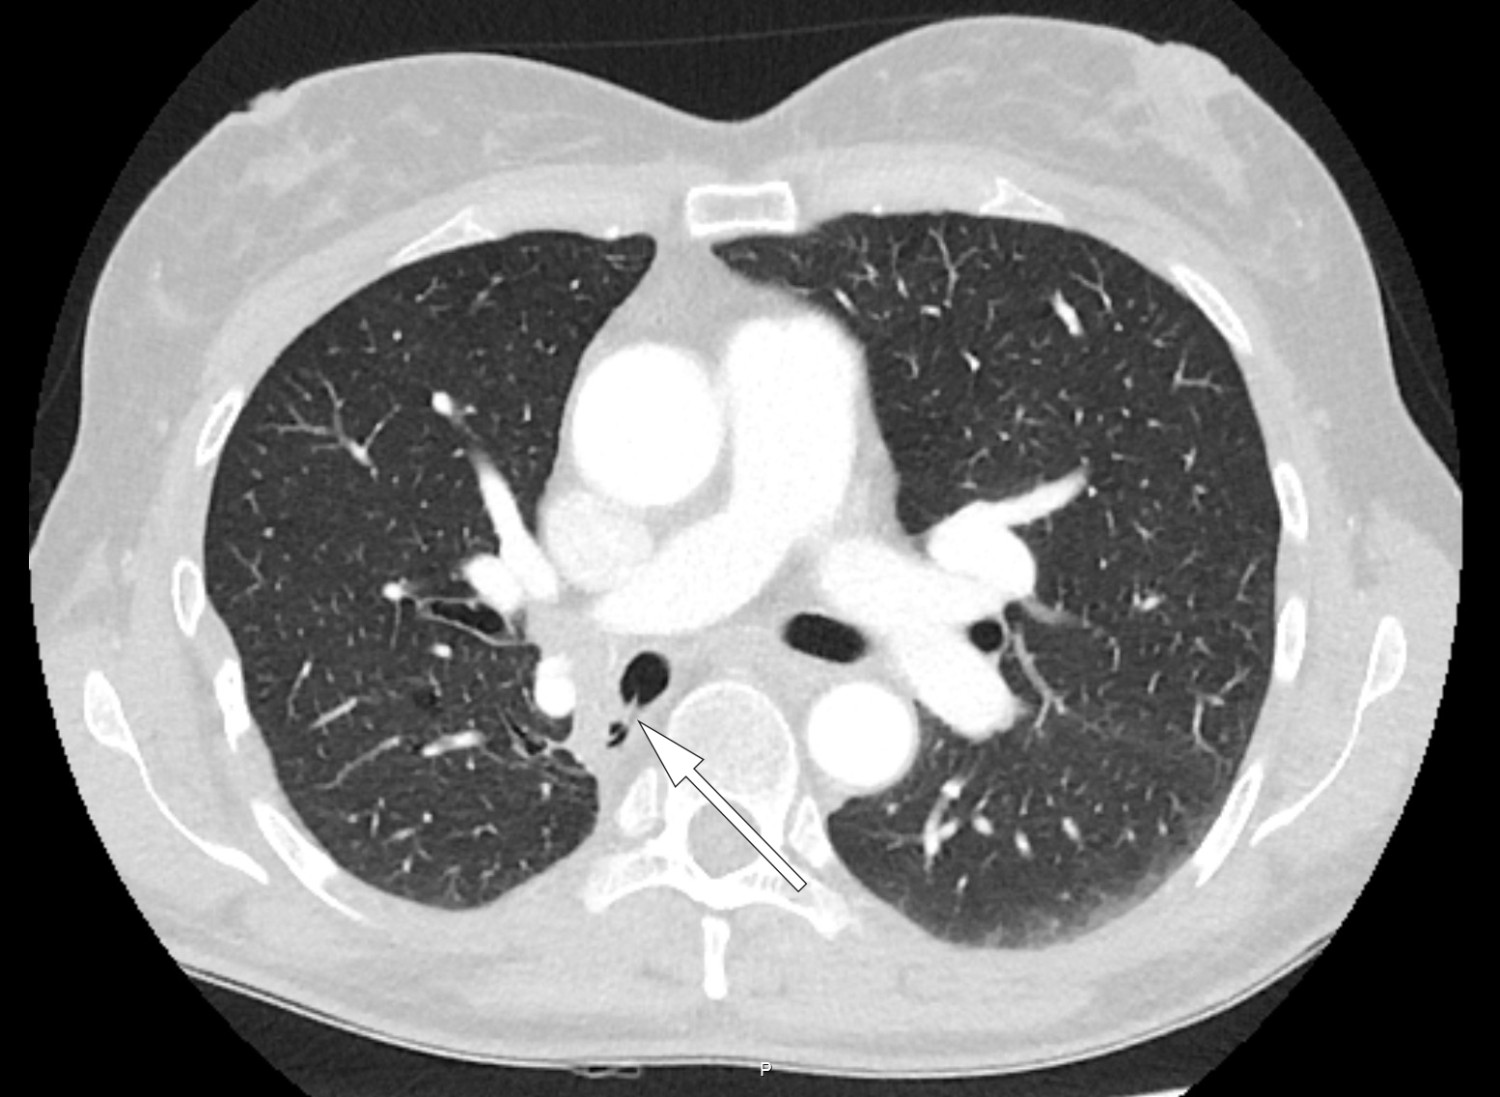

Pasienten er en kvinne i 50-årene. Som barn ble hun operert med partiell høyresidig underlappsektomi. Man lot det apikale underlappssegmentet stå igjen, og det ble brukt ikke-resorberbar tråd. Etter operasjonen har hun hatt tilbakevendende nedre luftveisinfeksjoner, alt fra bronkitt til pneumoni. Forut for den aktuelle bronkoskopien ble det gjort CT thorax som avdekket abscessutvikling (CT-bilde). Ved utredning fant man ingen underliggende immunsvikt eller andre forklaringer på infeksjonstendensen. Hun røyker daglig, men har ingen obstruktiv lungesykdom. Suturmaterialet som ble avdekket ved bronkoskopi var i retrospekt synlig på CT thorax-bildet, men kunne muligens mistolkes som sekret i luftveiene.

Suturmateriale er som et fremmedlegeme og fremmer dannelse av en biofilm og bakteriekolonisering. Dette er høyst sannsynlig årsaken til gjentatte pneumonier og utviklingen av lungeabscess (1) . De synlige suturene lot seg fjerne med tang bronkoskopisk. Prosedyren ble gjort først etter at pasienten hadde gjennomført langvarig antibiotikabehandling. Selv om det hadde gått mer enn 40 år siden operasjonen fant sted, var ikke suturmaterialet brutt ned. I litteraturen har vi funnet bare få rapporter om fjerning av aspirert fremmedlegeme med tilsvarende tidsspenn fra aspirasjon til fjerning (2) . I disse tilfellene har indikasjonen for utredningen vært tilbakevendende pneumonier, slik som hos vår pasient. Det vi kan lære av kasuistikken, er at hos pasienter med gjentatte nedre luftveisinfeksjoner av ukjent årsak bør man vurdere CT thorax og bronkoskopi.